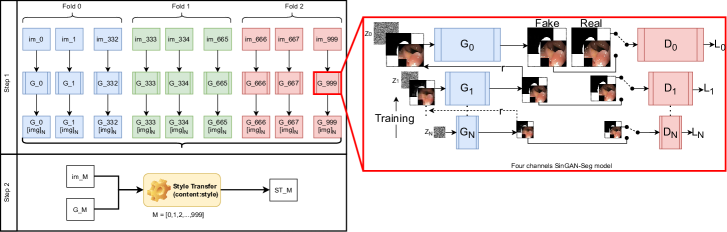

In the SinGAN-Seg pipeline, there are as depicted in Fig 1 two main steps: (1) training novel SinGAN-Seg generative models per image and (2) style transfer per image. The first step generates synthetic polyp images and the corresponding binary segmentation masks representing the polyp area. Our method, which is based on the vanilla SinGAN architecture [56], can generate multiple synthetic images and masks from a single real image and the corresponding mask. Therefore, this generation process can be identified as an generation process. Fig 1 represents this generation using , where represents the number of samples generated using our model and from a real image . Then, we apply this step for every image in a target dataset, for which we want to generate synthetic data. The second step focuses on transferring styles such as features of polyps’ texture from real images into the corresponding generated synthetic images. This second step is depicted in the Step 2 in Fig 1. This second step is also applied per image.

SinGAN-Seg is a modified version of SinGAN [56], which was designed to generate synthetic data from a GAN trained using only a single image. The original SinGAN is trained using different scales (from to ) of the same input image, the so-called image pyramid. This image pyramid is a set of images of different resolutions of a single image from low resolution to high resolution. SinGAN consists of a GAN pyramid to train using the corresponding image pyramid. In our study, we build on the implementation and the training process used in SinGAN, except for the number of input and output channels. The original SinGAN implementation [56] uses a three-channel RGB image as input and produces a three-channel RGB image as output. However, our SinGAN-Seg uses four-channel images as the input and the output. The four-channel image consists of the three-channel RGB image and the single-channel ground truth segmentation mask by stacking them together as depicted in the SinGAN-Seg model in Fig 1. The main purpose of this modification is to generate four-channel synthetic output, which consists of a synthetic image and the corresponding segmentation mask. We have done internal modifications to the vanilla SinGAN to handle four-channel input and output.

In the second step of the SinGAN-Seg pipeline, we fine-tune the output of the four-channel SinGAN-Seg model using the style-transfer method introduced by [57]. This method is also called Neural-style or Neural-transfer, which can take an image and reproduce a new image with a new artistic style. This algorithm calculates two distances, the content distance () and the style distance () to the third image. In the training process of this algorithm, contents and styles are transferred to the third image using the ratio. More information about this algorithm can be found in the original paper [57]. Using this style transfer algorithm, we aim to improve the quality of the generated synthetic data by transferring realistic styles from real images to synthetic images. As depicted in Step in Fig 1, every generated image is enhanced by transferring style form the corresponding real image . Then, the style transferred output image is presented using where in this study, representing the images in the training dataset. In this process, a suitable ratio should be found, and it is a hyper-parameter in this second stage. However, this step is a separate training step from the training step of the SinGAN-Seg generative models. Therefore, this step is optional to follow, but we strongly recommend this style-transferring step to enhance the quality of the output data from the first step.

Training Generators

Synthetic data versus real data for segmentation

We have performed three-fold cross-validation to compare the polyp segmentation performance using UNet++ when using either real or synthetic data for training. First, we divided the real dataset ( polyp images and the corresponding segmentation masks) into three folds. Then, the trained SinGAN-Seg generative models and the corresponding generated synthetic data were also divided into the same three folds. These three folds are presented using three colors in Step I of Fig 1. In the other experiments, training data and synthetic data folds were not mixed with the validation data folds. If mixed, it leads to a data leakage problem [62].